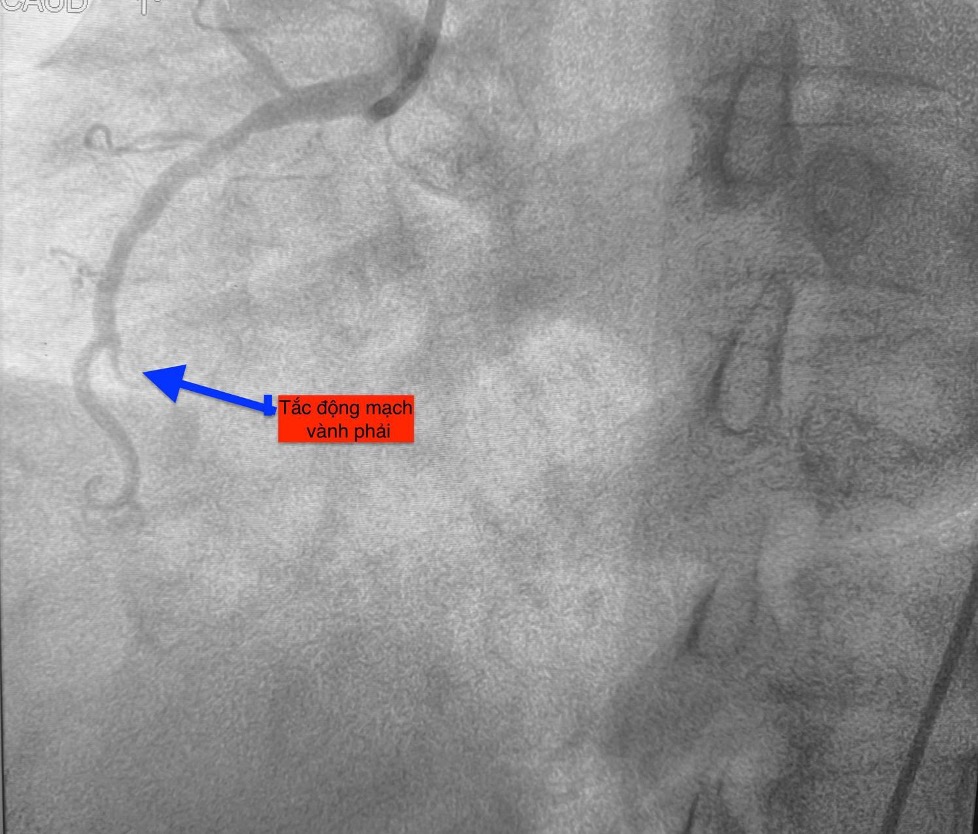

Trường hợp thứ nhất, lúc 0 giờ 34 phút ngày 14.11, nam bệnh nhân 51 tuổi vào bệnh viện vì mệt và khó thở. Chụp mạch vành phát hiện bệnh nhân bị tắc hoàn toàn động mạch vành phải.

Trường hợp thứ hai, lúc 9 giờ 5 phút, nam bệnh nhân 53 tuổi nhập viện vì chóng mặt và nóng rát thượng vị. Điện tâm đồ ghi nhận nhồi máu cơ tim cấp vùng dưới. Kết quả chụp mạch vành xác định bệnh nhân cũng bị tắc động mạch vành phải.

Trường hợp thứ ba, lúc 15 giờ 53 phút, nam bệnh nhân 78 tuổi nhập viện vì đau ngực. Bệnh nhân cho biết đau ngực từng cơn trong 3 ngày, ngày nhập viện thì đau ngực liên tục. Điện tim gợi ý nhồi máu cơ tim cấp; chụp mạch vành cấp cứu phát hiện bệnh nhân cũng tắc động mạch vành phải.

Hình ảnh chụp mạch vành cho thấy các bệnh nhân bị tắc mạch máu tim (do mảng xơ vữa, huyết khối) dẫn đến tình trạng thiếu máu cục bộ và nhồi máu cơ tim cấp